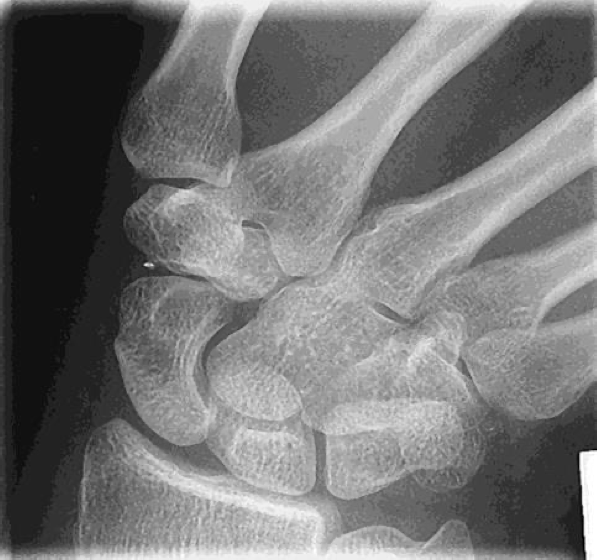

Evaluation Criteria for PA Wrist

• Distal radius/ ulna and carpals demonstrated

• Ulnar styloid process in profile

If humerus is not abducted & elbow flexed: the ulnar styloid process will not be in profile

• Open (or near open) radioulnar joint

• Center of field at midcarpals

• Long axis of 3rd metacarpal in line with long axis of forearm

• No rotation

• Exposure factors

Good soft tissue

Should demonstrate scaphoid fat stripe